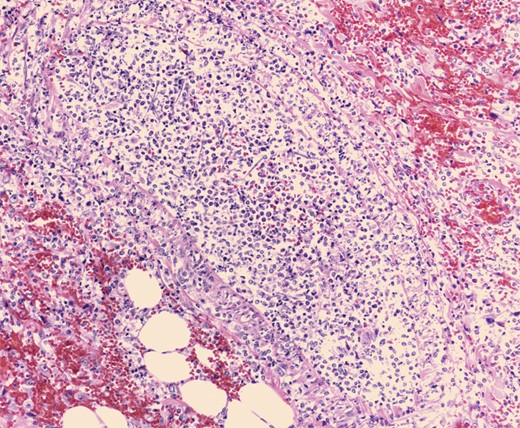

Pathologic evaluation of the resected bowel revealed hemorrhagic, gangrenous bowel (Fig. 1) and granular friable, ulcerated mucosa (Fig. 2). Microscopically, there were areas of transmural bowel necrosis (Fig. 3) and fungi within the bowel wall, artery wall and lumen (Fig. 4). Gomori Methenamine Silver stain was characteristic of Aspergillus species (Fig. 5).

Admixed blood clot and fecal material, focally adherent to the granular, friable mucosa with associated exudate and edema.